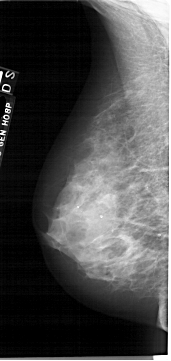

A_1877_1.RIGHT_MLO

LEFT_MLO LINES 6481 PIXELS_PER_LINE 3061 BITS_PER_PIXEL 12 RESOLUTION 43.5 NON_OVERLAY